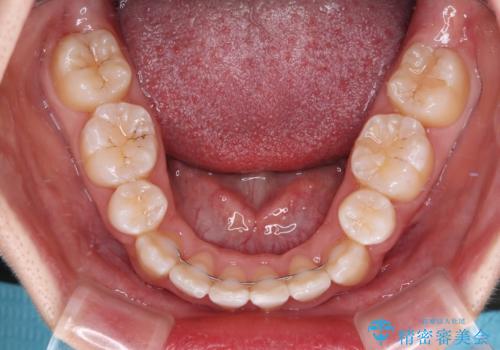

デコボコの解消で歯が磨きやすくなり、抜歯矯正により口元の突出感が大幅に改善され、スッキリした口元になりました。